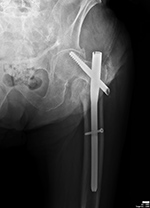

| Left hip cannulated screw fracture |

| 41 year-old man with chronic left femoral neck fracture and fracture of superior cannulated fixation screw. The partially visualized intramedullary nail is for an old femoral shaft fracture. |